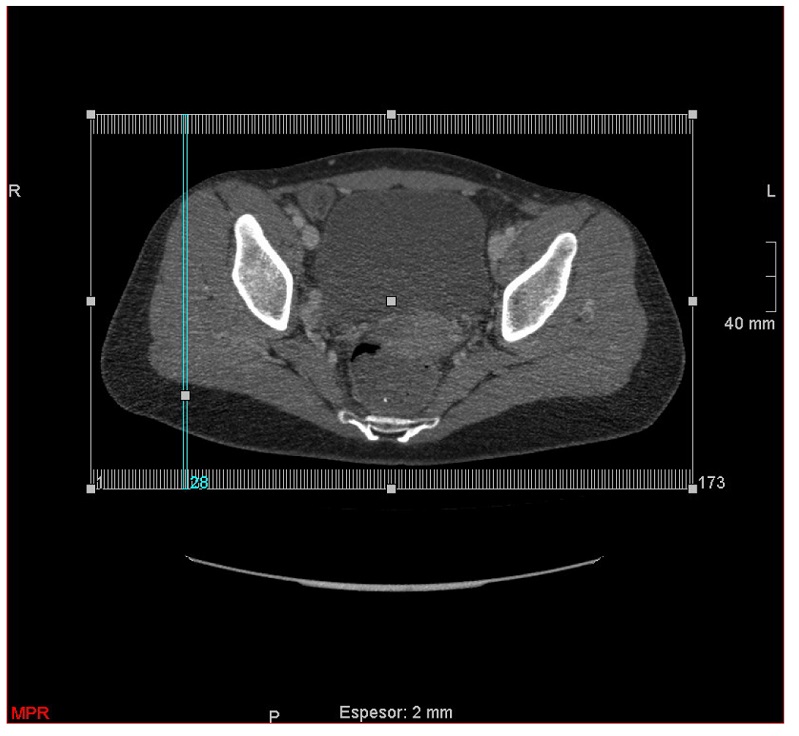

Ante estos hallazgos se decidió hacer TAC pélvico y se confirmó que había discreto realce poscontraste que podía corresponder con un quiste del canal de Nuck complicado (figura 2). Se visualizó permeabilidad de estructuras vasculares ilíaca y femorales, pequeña adenopatía inguinal de aspecto reactivo.

El TAC o la RNM pueden ser útiles para visualizar la relación anatómica para el diagnóstico diferencial y el abordaje quirúrgico.